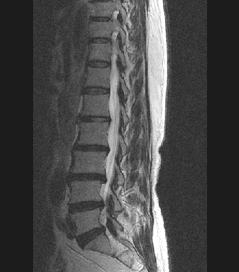

HLD on L-spine, Lt. L5 & S1 Radiculopathy

64세 여자환자는 2개월 전부터 요통과 다리 바깥쪽과 발등, 종아리 뒤쪽으로 저린 감각이 심해져서 개인병원에 들러 평가 및 물리치료를 받았으나 별다른 호전이 없고, 1주일 전부터는 허리를 숙이거나 물건을 들 때, 오래 걸을 때 통증이 더 심해져서 본원을 방문하였다. 12년전 집안일을 심하게 하고 난 후부터 간헐적인 요통을 발생하였으며, 별다른 치료 없이 지냈으며, 4년전 무거운 물건 들고 난 후 심하게 요통과 둔부의 통증까지 발생하여 MRI 촬영상 L1-2, L3-4-5, L5-S1 HNP와 Lt. L4 & both L5 nerve compression, Lt. S1 nerve compression 진단받고 Epidural steroid injection을 받고 통증 경감되었고, 간헐적으로 통증이 발생하였으나 별다른 치료 없이 헬스클럽에서 지속적인 운동으로 관리하였다.

• 척추 방사선 사진2